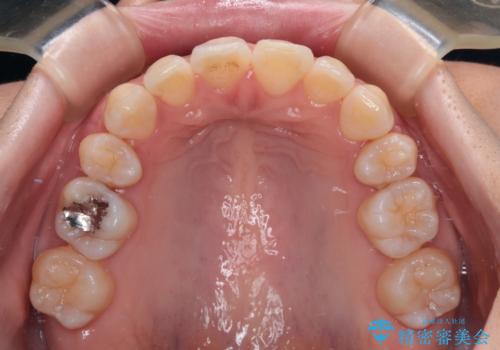

舌の突出癖がなかなか改善されず、上下前歯の接触がやや甘い状態での仕上がりとなりました。

接触が甘い場合、上顎前歯の叢生が後戻りを起こしやすくなるため、治療終了後の保定期間でも舌のトレーニングを継続するように指示しています。